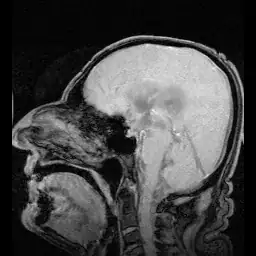

This image from Wikipedia shows "circulation" that normally occurs with heartbeat.

MRI showing pulsation of CSF